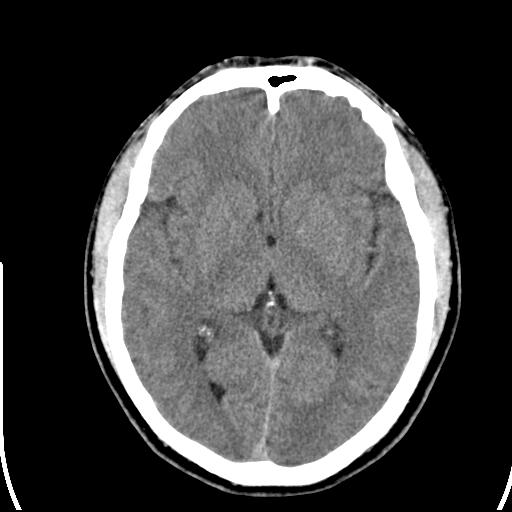

标题: CT25435:头皮下高密度影???

头皮下高密度结节影???临床上在老年男性比较常见。大家看看是什么?成因是? 本例患者,男性,51岁。外伤来诊。无染发史及发根植入史。